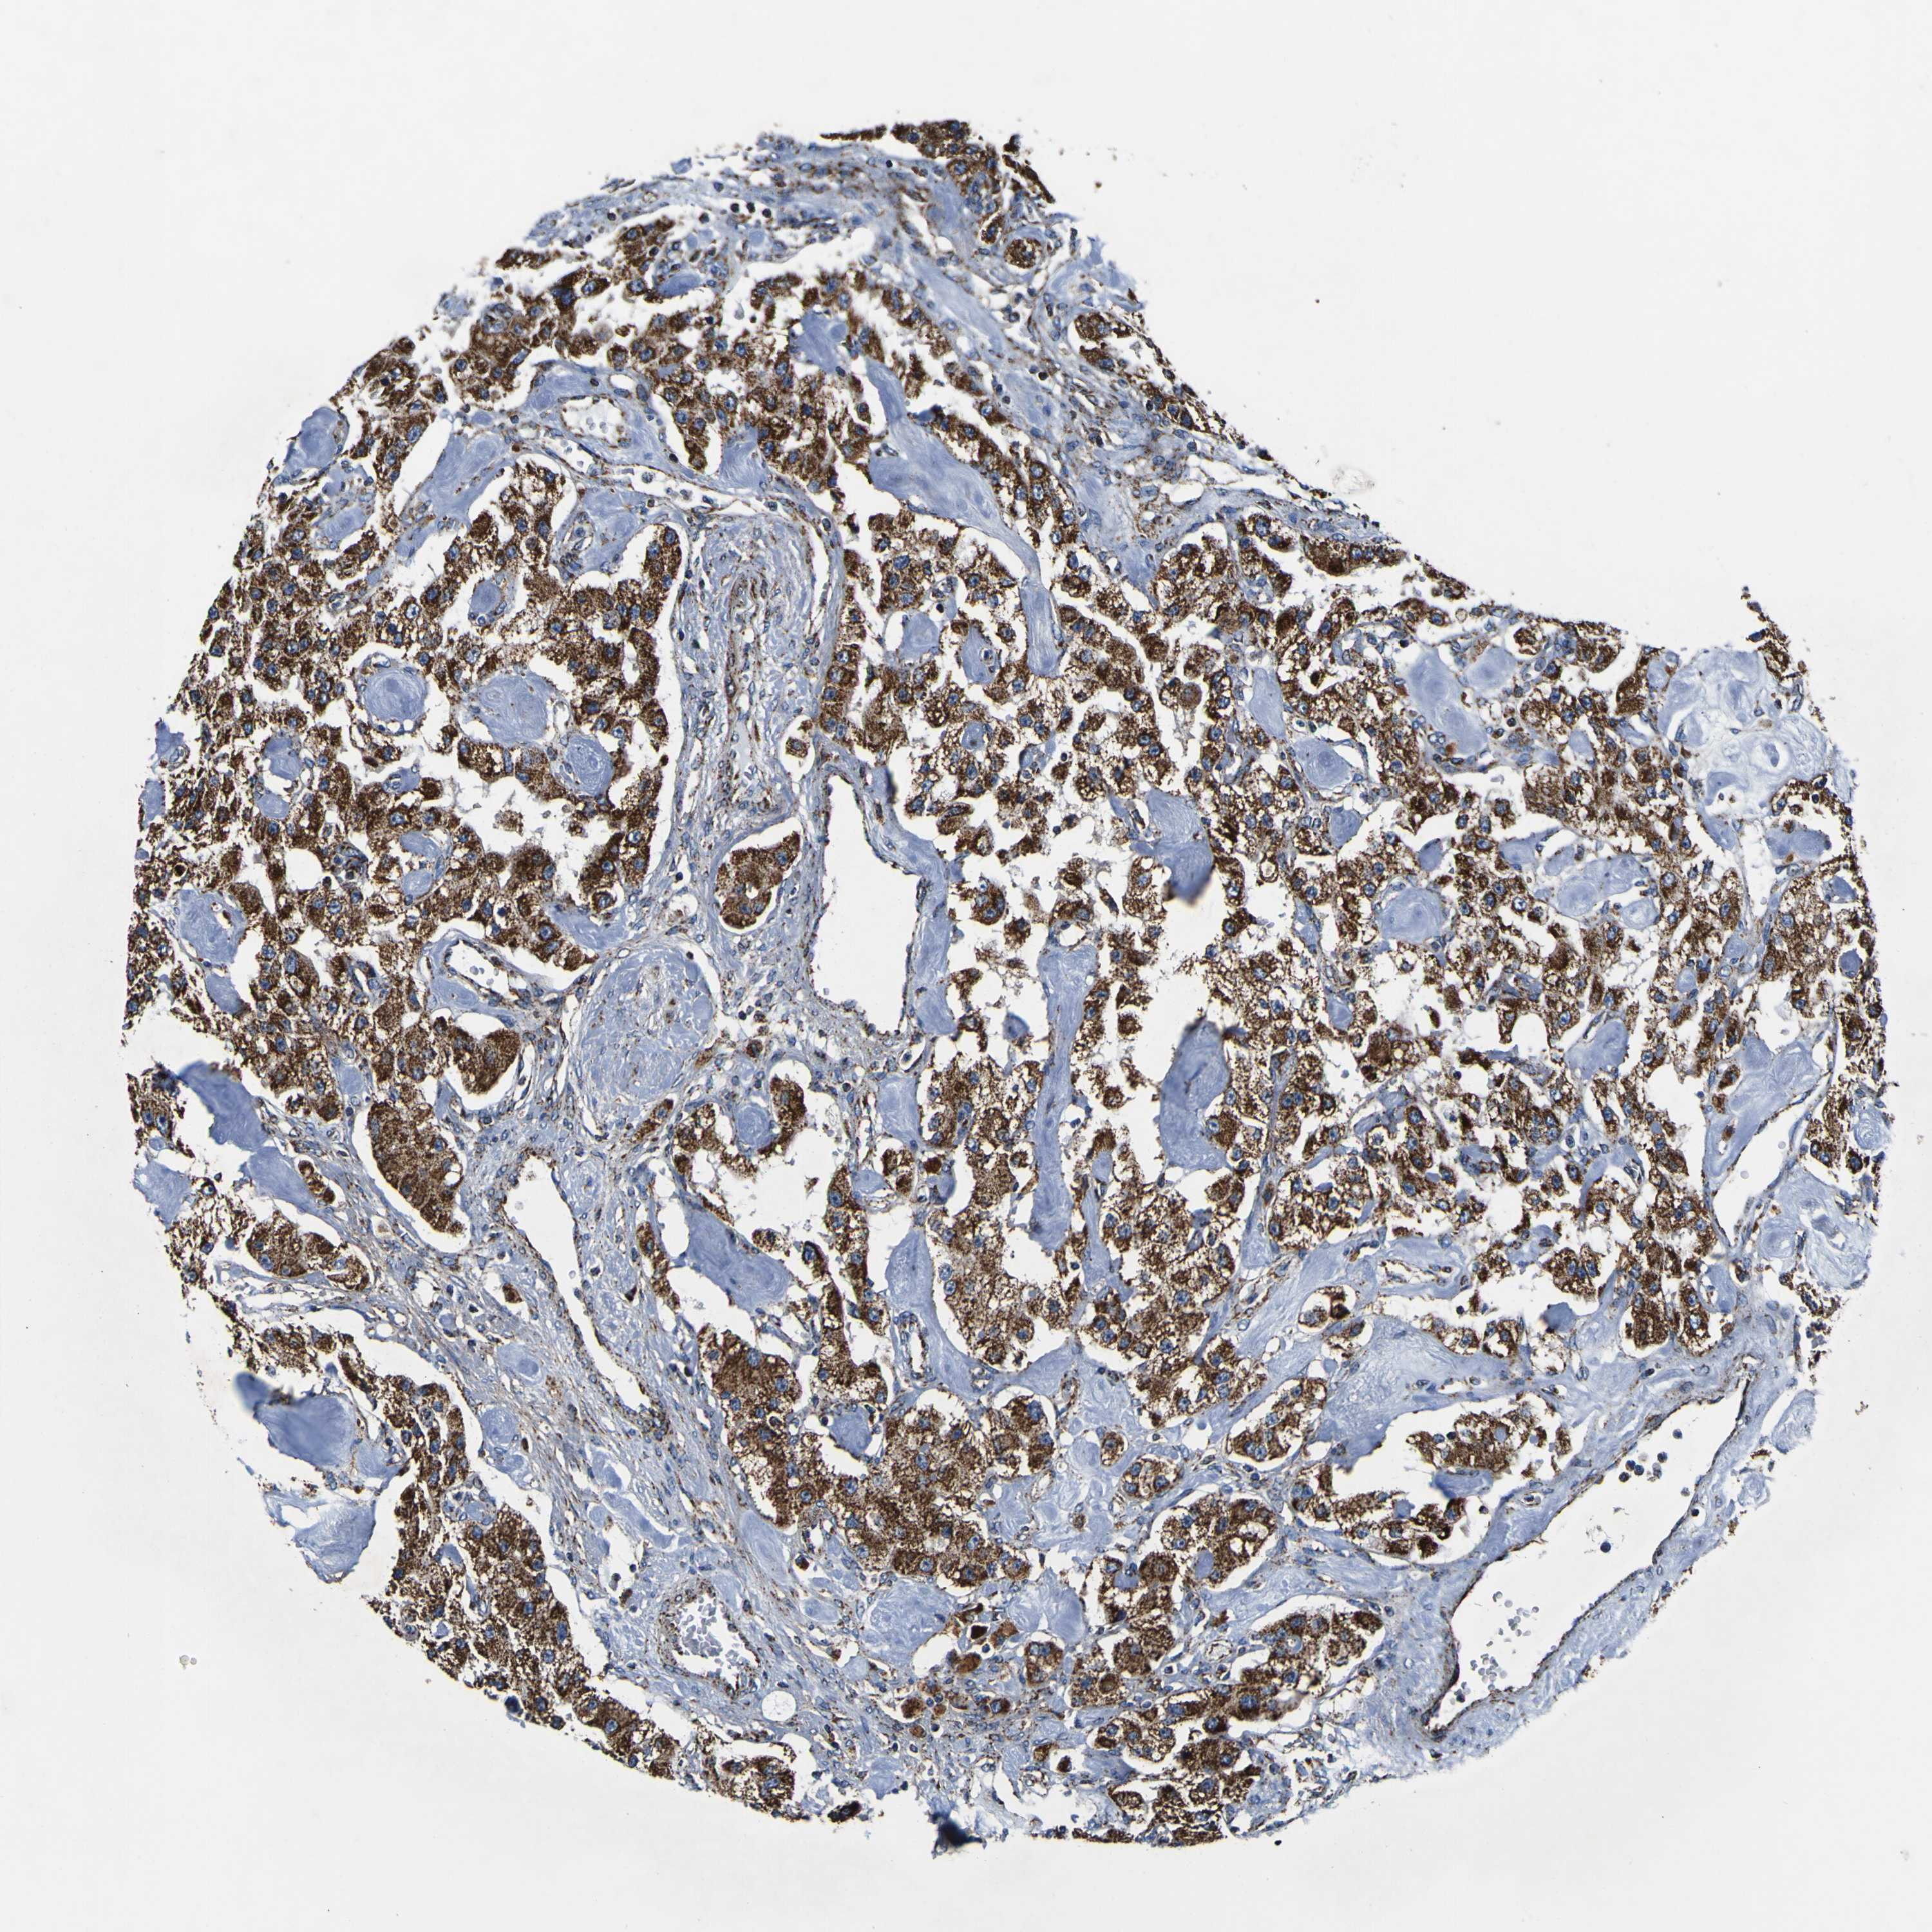

CARCINOID - Protein expressioni

A mouse-over function shows sample information and annotation data. Click on an image to view it in a full screen mode. Samples can be filtered based on level of antibody staining by selecting one or several of the following categories: high, medium, low and not detected. The assay and annotation is described here.

Antibody stainingi

Antibody staining in the annotated cell types in the current human tissue is reported as not detected, low, medium, or high, based on conventional immunohistochemistry profiling in selected tissues. This score is based on the combination of the staining intensity and fraction of stained cells.

Each image is clickable and will lead to virtual microscopy that enables deeper exploration of all samples and also displays staining intensity scores, fraction scores and subcellular localization as well as patient and tissue information for each sample.

Antibody HPA012897

Staining

High

Intensity

Strong

Quantity

>75%

Location

Nuclear

Cytoplasmic/membranous

Carcinoid, malignant, NOS